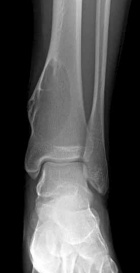

T.K. - 18 year old male with asymptomatic left ankle swelling for several months